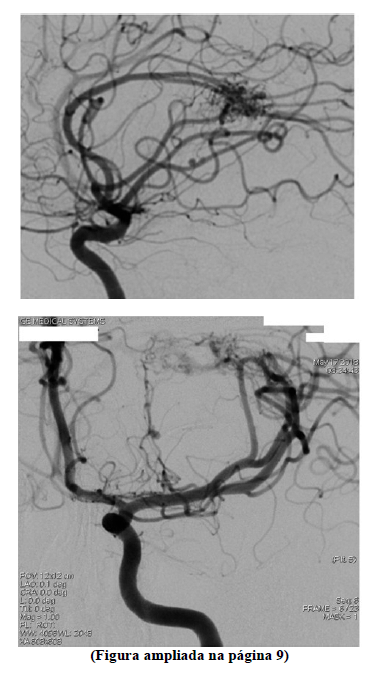

Um homem de 42 anos de idade é levado à emergência pelos vizinhos, que relatam que o encontraram caído, sem conseguir movimentar o lado direito ou falar. A mãe relatou que, há dois dias, o paciente iniciou com cefaleia e nucalgia, tratadas como quadro hipertensivo na unidade básica de saúde. Ao exame: PA = 137 mmHg x 79 mmHg, FR = 16 ipm, FC = 96 bpm, SaO2 = 98% em ar ambiente e glicemia capilar = 125 mg/dL, com paciente alerta, afásico, com hemiparesia direita (força grau 1), paralisia facial central à direita e pupilas isocóricas e fotorreagentes, obedecendo a comandos verbais à esquerda. Uma tomografia do crânio sem contraste evidenciou hemorragia intraparenquimatosa em núcleos da base à esquerda com pequeno efeito compressivo em ventrículo lateral esquerdo, sem desvio de linha média. Foi realizada uma angiografia digital.

Com base nesse caso clínico e nas imagens da angiografia digital apresentadas e conhecimentos médicos correlatos, julgue os itens a seguir.